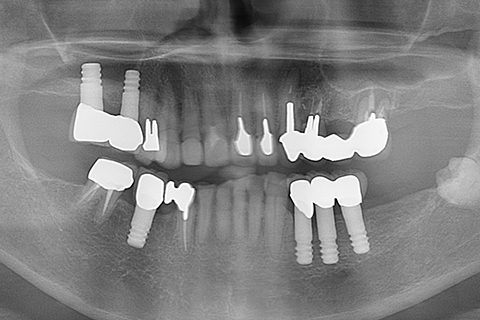

症例4

治療前

治療後

- 年齢・性別

- 60歳

- 治療期間

- 6ヶ月

- 抜歯

- 残根抜歯のみ

- 治療費

- 184.8万円

- 備考

- 右上5.6 右下5 左下4.5.6欠損

- 治療内容

- 6本のインプラントを右左側に2回に分けて埋入

- 施術の副作用(リスク)

- オペによる知覚障害。インプラントによる歯肉炎。インプラント脱落。